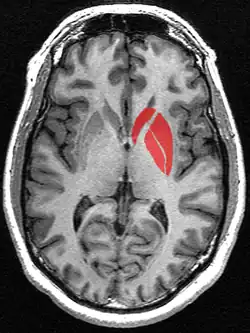

| Striatum | |

![]() Tractography showing corticostriatal connections | |